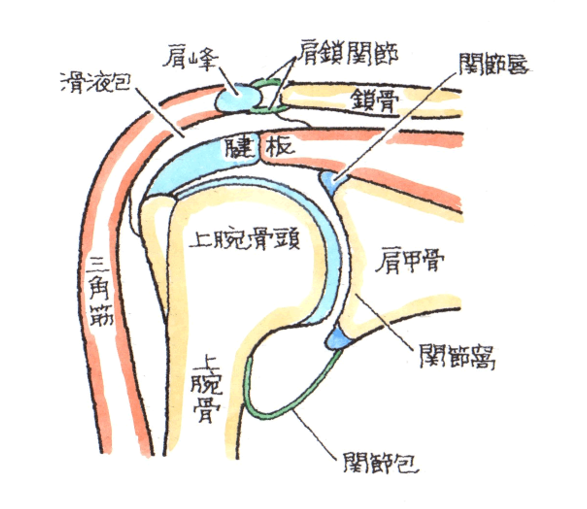

腱板損傷 腱板断裂 のリハビリから手術まで 医療法人社団景翠会 金沢病院グループ

肩 脳卒中にならないためのリハビリテーション

肩関節インピンジメント症候群 電子コンテンツ 日本医事新報社